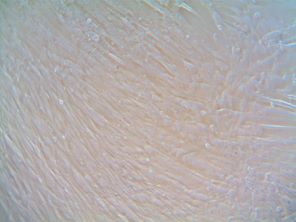

Human Bronchial CAFs

Human Bronchial CAFs |